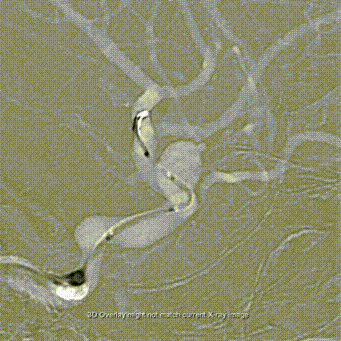

Lattice支架释放:

Lattice支架过弯释放:

Lattice支架全释放:

Lattice支架内按摩:

术后支架贴壁良好: